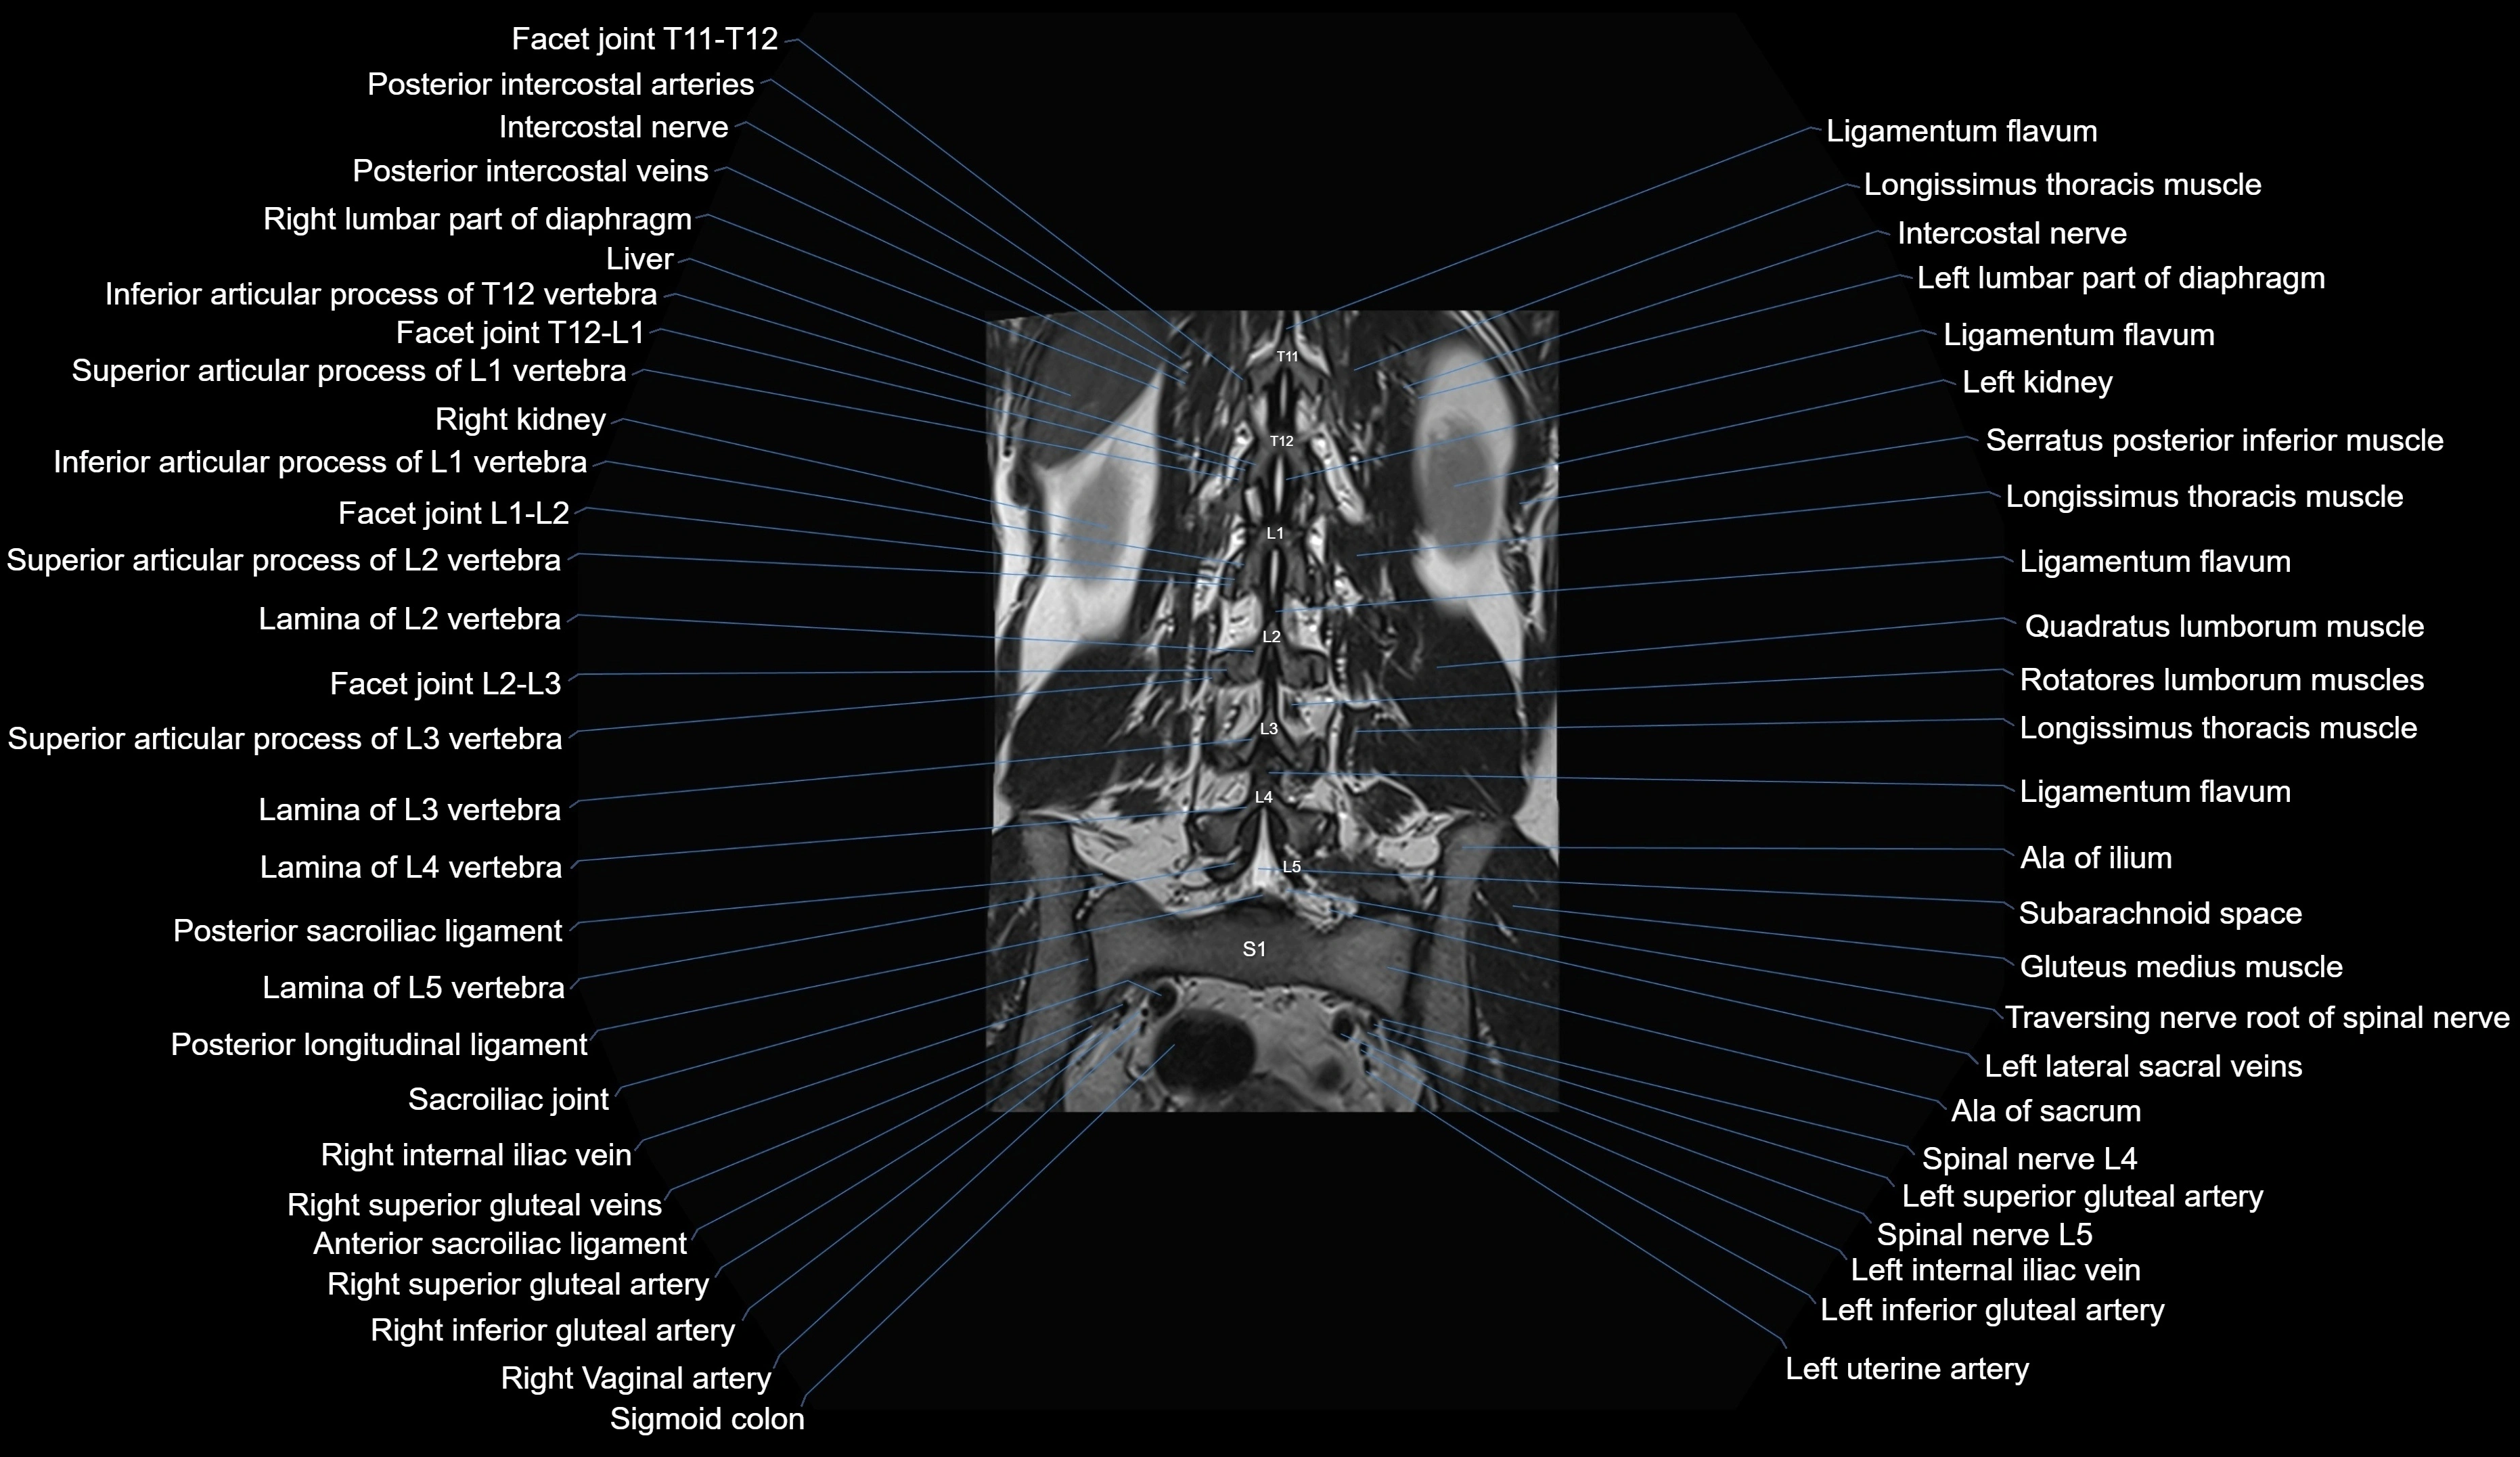

MRI images